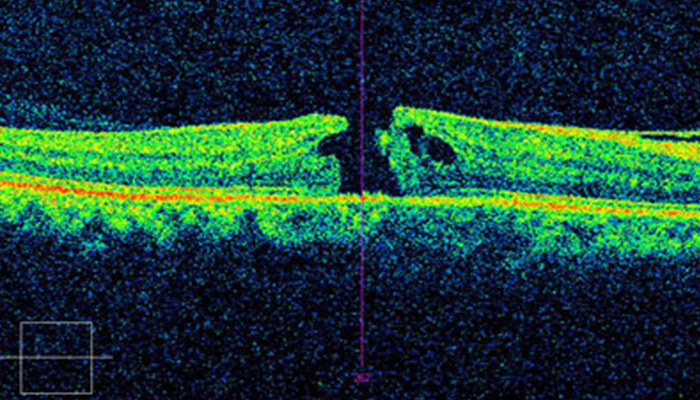

Macular Hole

macular hole is a small break or tear in the macula, the central part of the retina responsible for sharp, detailed vision used for activities like reading, driving, and recognising faces and any damage to it can significantly impair visual clarity.

Age related and more common in people over 60, a macular hole typically occurs due to changes in the vitreous, the gel-like substance inside the eye. As we age, the vitreous can shrink and pull away from the retina, sometimes causing a tear or hole in the macula.